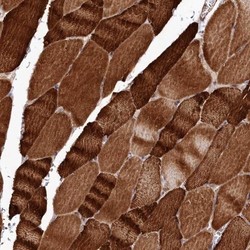

Immunohistochemistry

NBP1-85666 IHC

Full details

Other validation